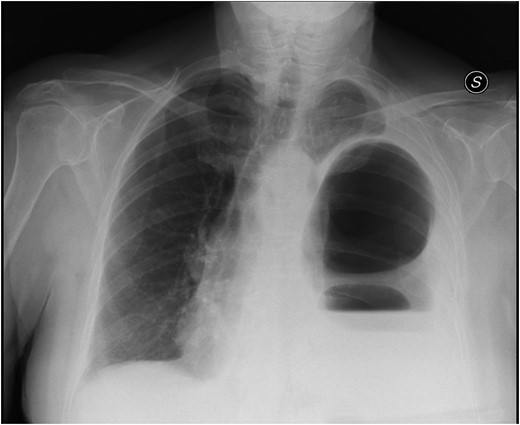

In April 2011, a 73-year-old woman with history of left-pancreatectomy and splenectomy for a neuroendocrine tumour (2009) was admitted to the emergency department with abdominal cramps, nausea, without vomit or dyspnea. Her anamnesis was negative for asthma, respiratory distress, blunt or penetrating trauma or conspicuous weight loss. Abdominal examination showed a diffusely painful protruding abdomen, without signs of peritonitis and Blumberg sign was negative. Chest radiographs (Fig. 1) showed a raised left hemidiaphragm, with bowel herniation into the lower half of the left hemi-thorax.